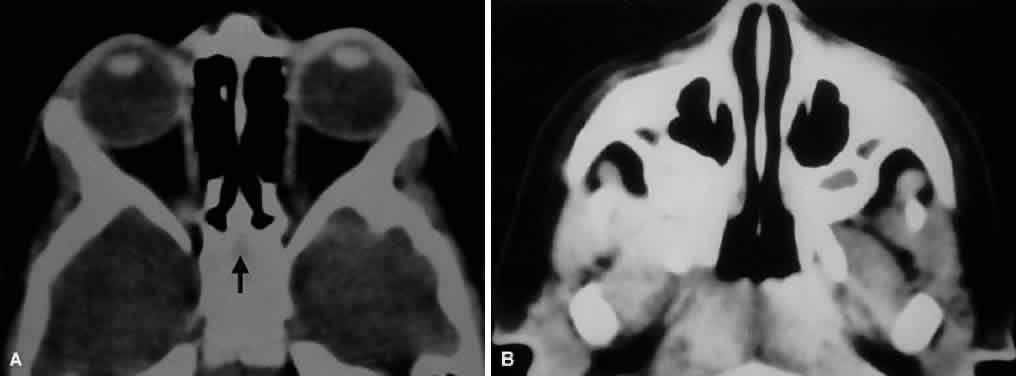

Fig. 5. Axial CT of paranasal sinus development in a 2-year-old child. A. Note that the ethmoid air cells are pneumatized, but the future sphenoid sinus is seen only as a faint lucency (arrow) within surrounding bone. B. Rudimentary maxillary sinuses have already partially pneumatized.